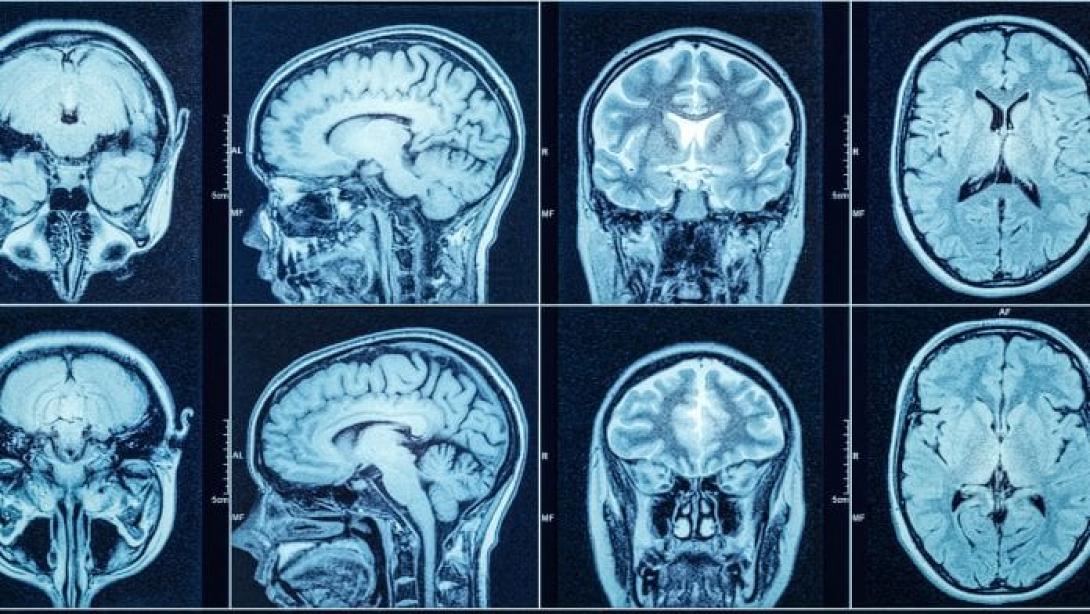

εγκεφαλος

Οι εγκέφαλοι ασθενών που πέθαναν από Covid-19 παρουσιάζουν συσσώρευση παθολογικών πρωτεϊνών που συνήθως παρατηρείται στη νόσο του Αλτσχάιμερ, διαπιστώνουν νέες μελέτες, οι οποίες δεν αποκλείουν το ενδεχόμενο να δημιουργεί ο κοροναϊός προδιάθεση για άνοια.

Στα εγκεφαλικά κύτταρα των θυμάτων του κοροναϊού συσσωρεύεται η λεγόμενη πρωτεΐνη ταυ και η πρωτεΐνη β-αμυλοειδές, βασικό εύρημα στους εγκεφάλους ανθρώπων που πεθαίνουν από Αλτσχάιμερ, δείχνουν οι τρεις νέες μελέτες.

Στο πανεπιστήμιο Κολούμπια της Νέας Υόρκης, η ομάδα του δρ Άντριου Μαρκς εξέτασε τους εγκεφάλους δέκα ανθρώπων που είχαν πεθάνει από βαριά Covid-19 και εντόπισε διαταραχή στη λειτουργία των υποδοχέων ρυανοδίνης, οι οποίοι ελέγχουν την είσοδο ιόντων ασβεστίου στα κύτταρα.

Στη νόσο Αλτσχάιμερ, οι προβληματικοί υποδοχείς ρυανοδίνης έχουν συνδεθεί με τη συσσώρευση της πρωτεΐνης ταυ σε παθολογικούς σχηματισμούς που ονομάζονται νευροϊνιδιακοί σωροί.

Τέτοιοι σωροί ανιχνεύονται σε υψηλά επίπεδα και στα θύματα της Covid-19, αναφέρει η ερευνητική ομάδα στην επιθεώρηση Alzheimer’s & Dementia.

Το ανησυχητικό εύρημα έρχεται να προστεθεί σε δύο άλλες μελέτες, οι οποίες παρουσιάζονται ως προδημοσιεύσεις στα αποθετήρια του bioRxiv και του Lancet, και δείχνουν ότι στους εγκεφάλους ασθενών που πέθαναν από Covid-19 συσσωρεύεται το λεγόμενο β-αμυλοειδές, μια δεύτερη πρωτεΐνη που συνδέεται με την Αλτσχάιμερ.